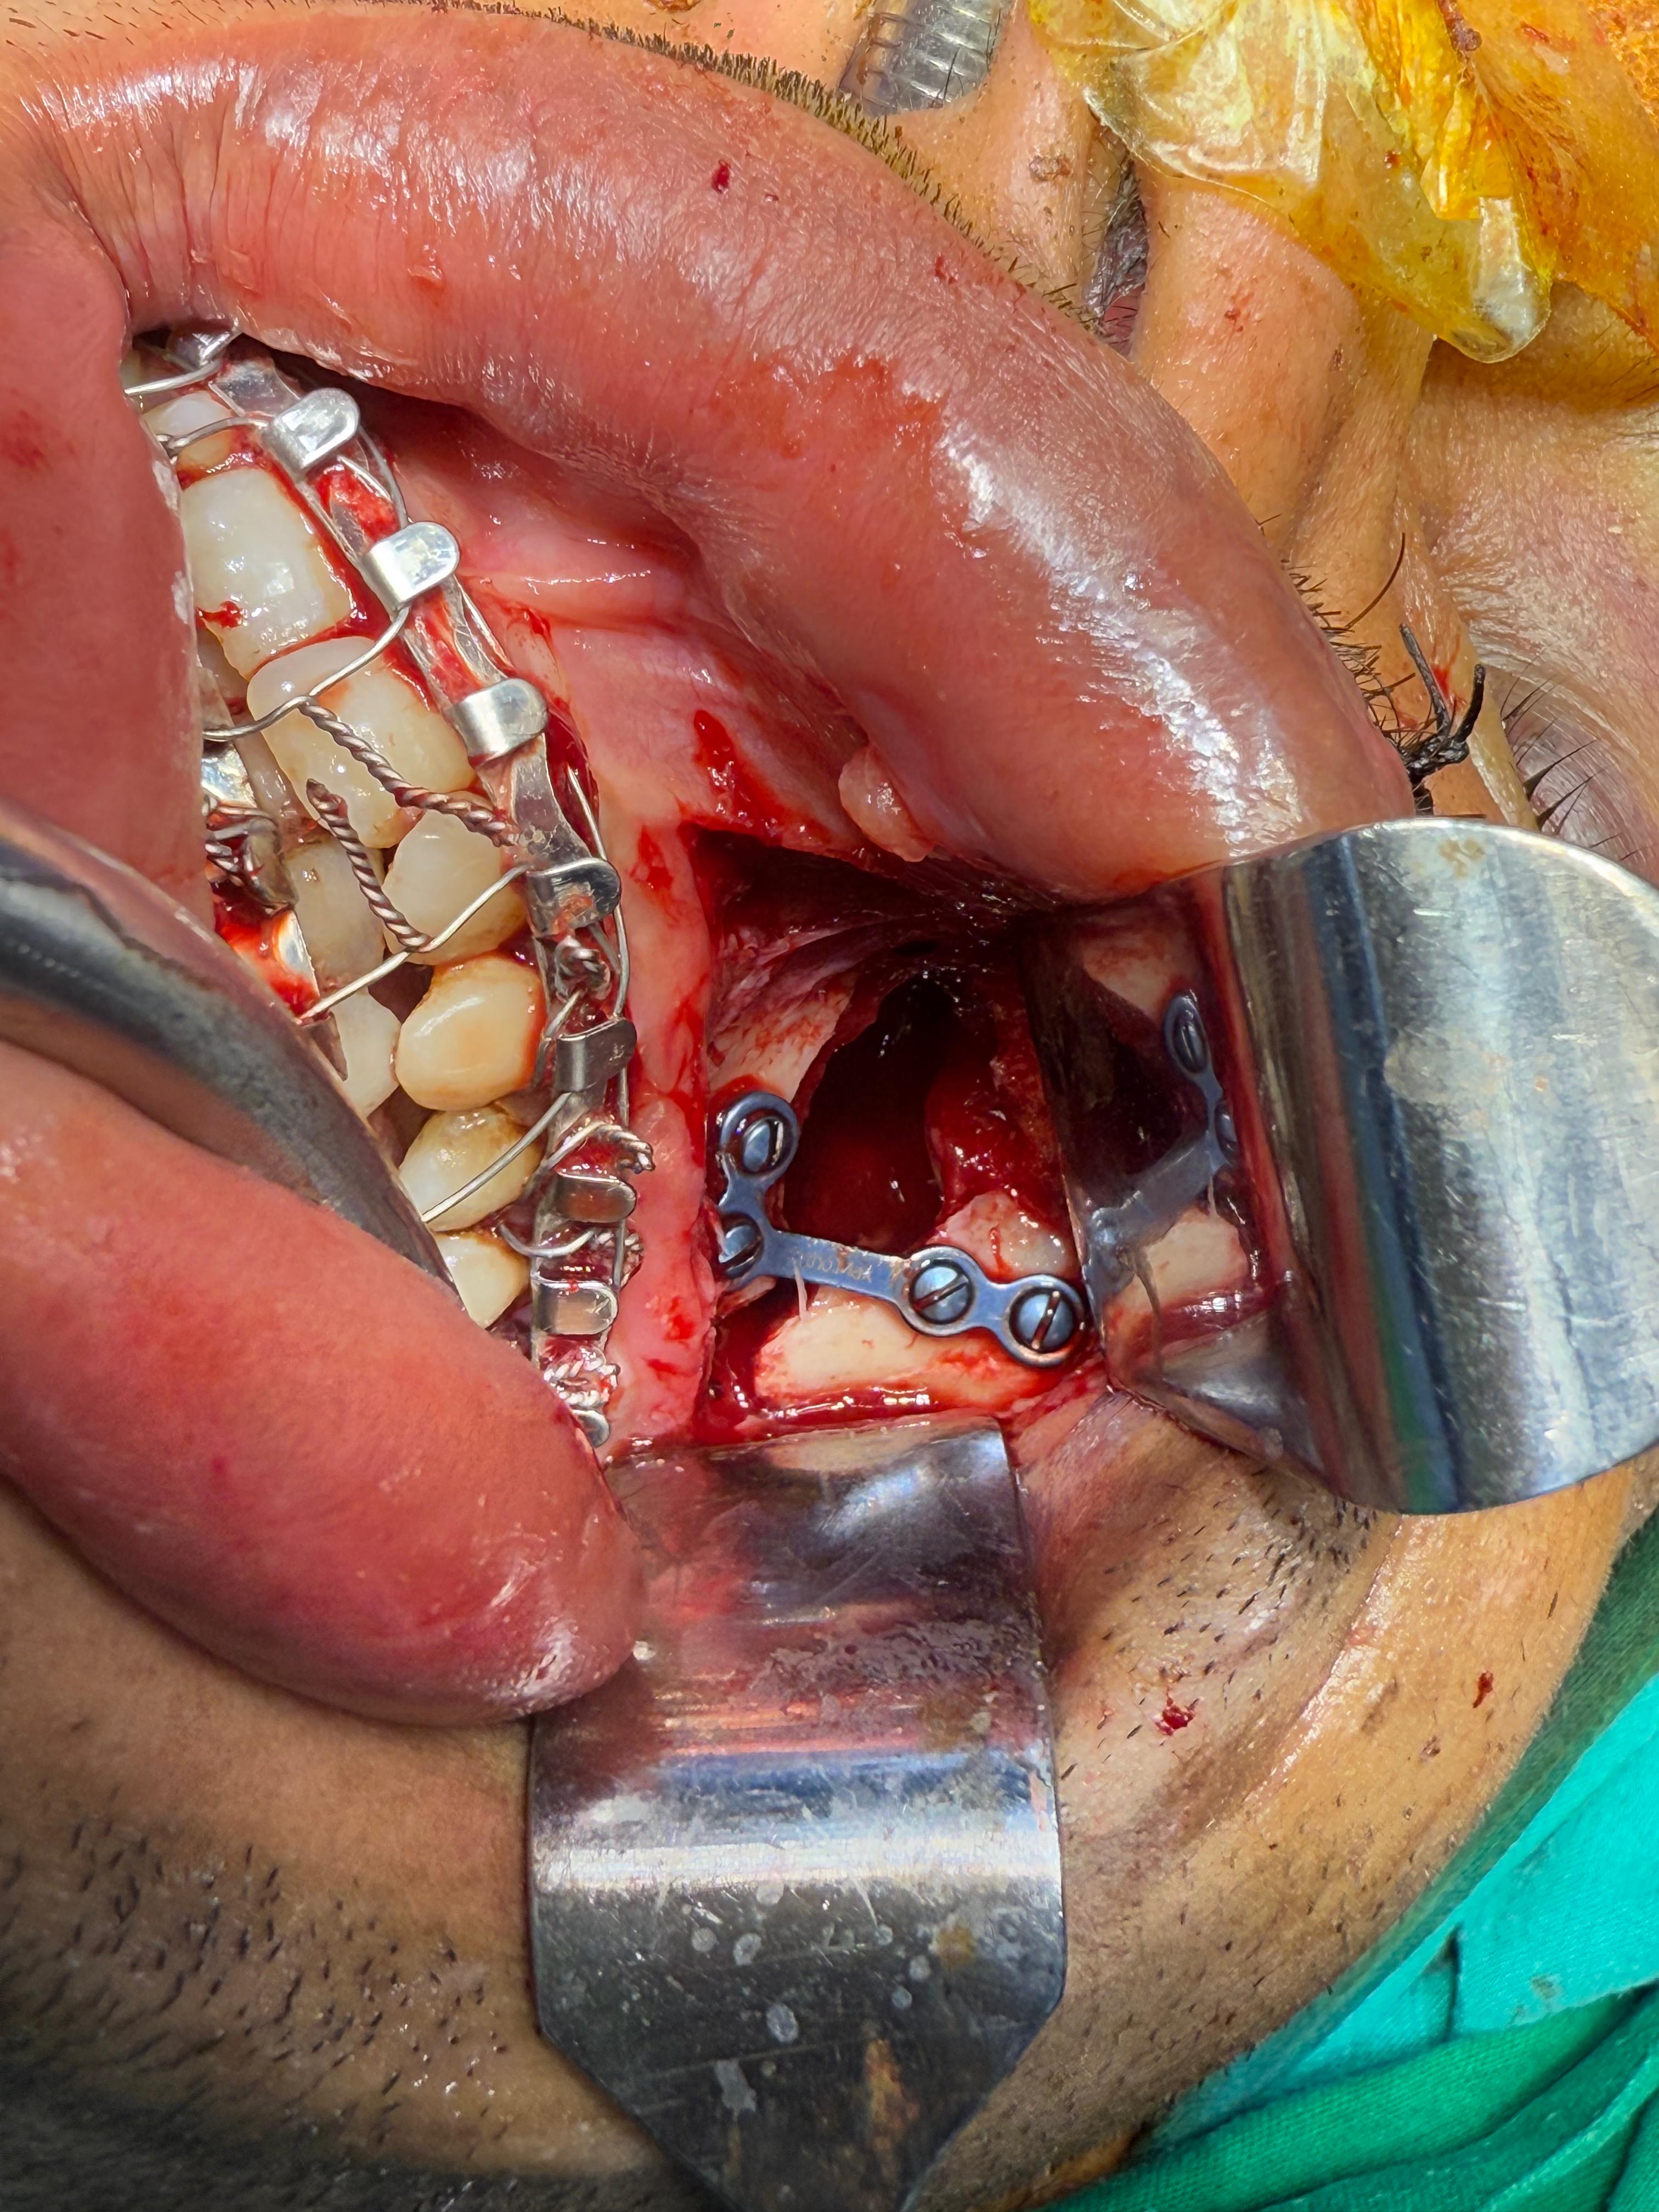

Department of Oral & Maxillofacial Surgery

Orthognathic (jaw corrective) surgeries

Orthognathic surgeries